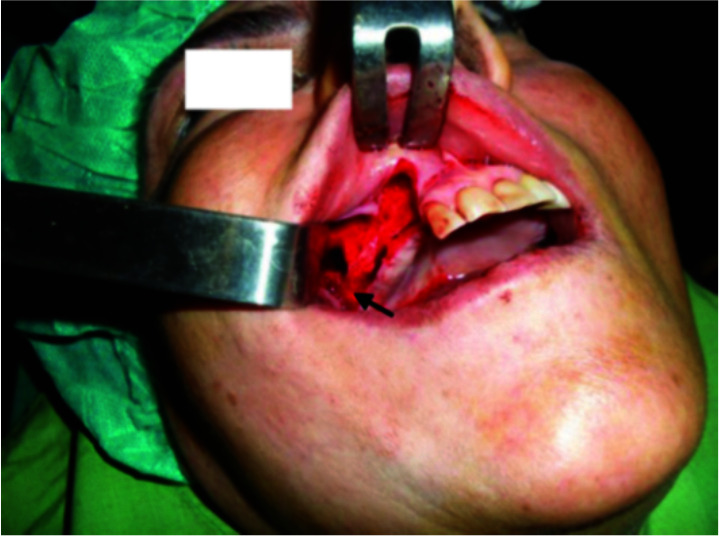

The use of dental implants to restore edentulous jaws has become commonplace. Usually, in the maxilla, following a tooth extraction, the height of alveolar bone decreases. This alteration in bone increases the risk of implants migrating into the sinus. In general, Caldwell-Luc and endoscopic surgery are performed to retrieve dental implants. In this case series, we collected data from 39 patients who had the complication of implant displacement within the maxillary sinus for 25 years. All the implants were removed using the Caldwell-Luc technique. Implant migration happened following functional loading, during the prosthetic procedure, due to lack of osseointegration in 3 patients, and during implant placement into the fresh socket in 3 patients. In the remaining cases, migration occurred preoperatively or postoperatively and prior to implant loading. Insufficient bone quantity is sometimes causing the implant to migrate to the maxillary sinus. In case of minimal bone height, a sinus lift before implant placement should be conducted. Retrieval of an implant pushed inside the maxillary antrum using the Caldwell Luc approach proved to be a reliable technique.